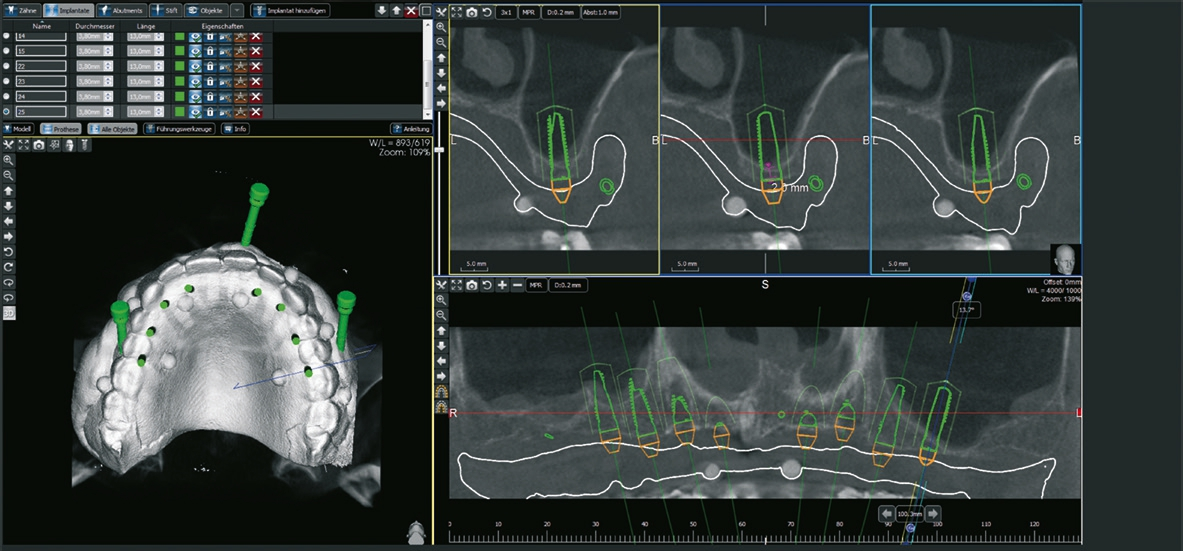

Das Angebot an minimalinvasiven Techniken nimmt nach wie vor zu: Da ist zum einen der Einsatz der digitalen Volumentomographie mit entsprechender Software zur Planung implantologischer Eingriffe und der Option zur Herstellung von Schablonen. Behandler werden in der operativen Umsetzung der digitalen Planung unterstützt. Aber auch das Angebot an Instrumenten und Geräten zur minimalinvasiven Chirurgie nimmt ständig zu. Beispielhaft seien an dieser Stelle piezochirurgisch unterstützte Techniken zur Kieferkammverbreiterung genannt. Aber auch die Indikationserweiterungen von Knochen- und Weichgewebsersatzmaterialien erlauben dem Behandler in zunehmendem Maße in vielen Behandlungsfällen den Verzicht von klassischen Zugangs- und OP-Techniken zu Gunsten der „flapless surgery“ respektive weniger invasiven Eingriffen. Patienten profi tieren unter anderem in den Aspekten der Schmerzsymptomatik, dem verkürzten Wundheilungsverlauf und des prothetischen „backward plannings“ mit der Möglichkeit der Zahnersatzpräfabrikation [1-5].

Patient 2: männlich, 71 Jahre alt, Anamnese: koronare Herzkrankheit; Diagnose: zahnloser Kiefer resp. nicht erhaltungswürdiger Zahn 11, insuffizienter Zahnersatz. Knochenersatzmaterial: maxgraft® (botiss) (Abb. 11 und 12).

Dr. van Orten